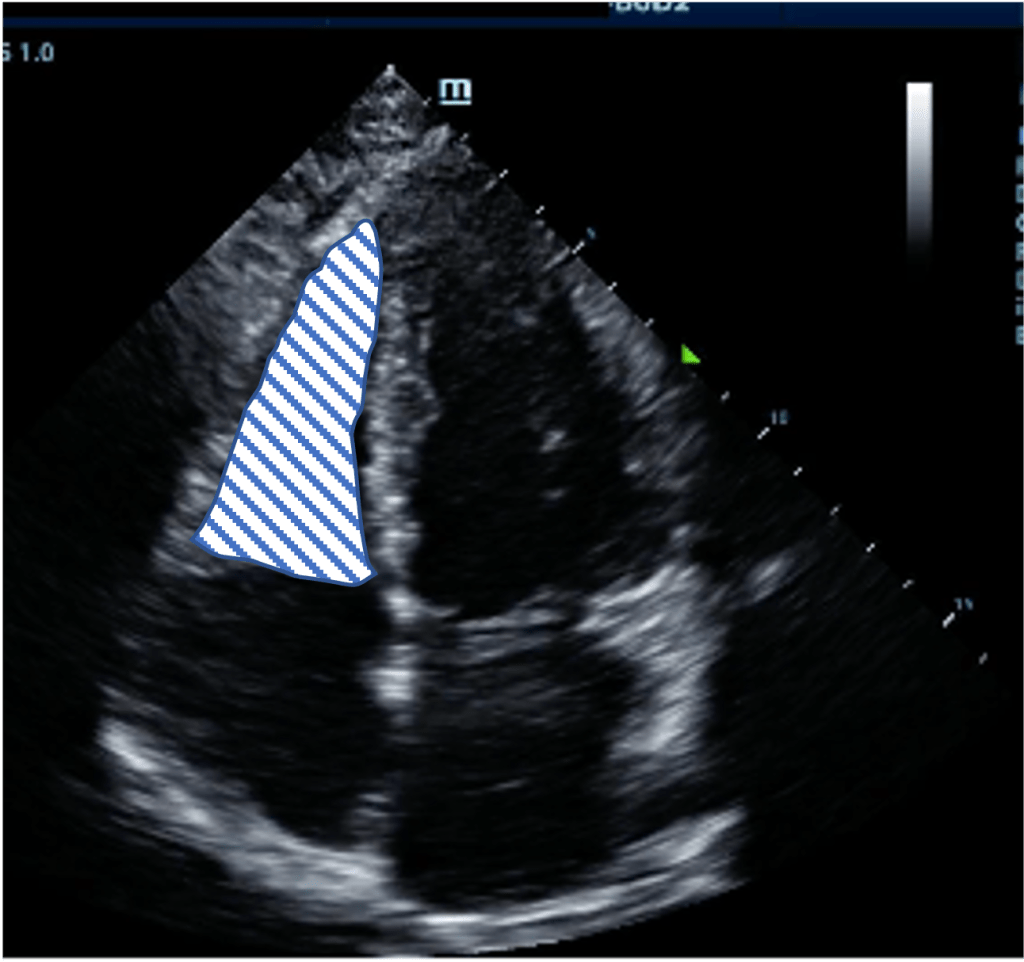

An area that is quite frought with error is the approach, in particular during a cardiac arrest, is to judge whether the RV is dilated as a sign of acute PE. Putting aside the fact that RV frequently becomes dilated during cardiac arrest regardless of the presence of embolus the subcostal view frequently underestimated RV signs as it is generally quite an inferior angle which tends to “shrink” the RV. The views below of the subcostal (left) and A4C (right) are from the same patient which while the RV appears impaired by visual TAPSE in the subcostal views and perhaps moderately enlarged as it is close in size to the LV we see this is a gross underestimate when viewing from the A4C an RV that is dwarfing it neighbour.